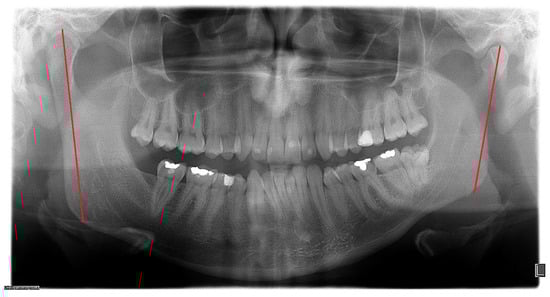

R—ramus vertical height increased (Figure 6)—the distance from the top of condyle head to gonial angle increased, typical for HH cases;

Figure 6. The increased vertical dimension of the mandibular ramus.